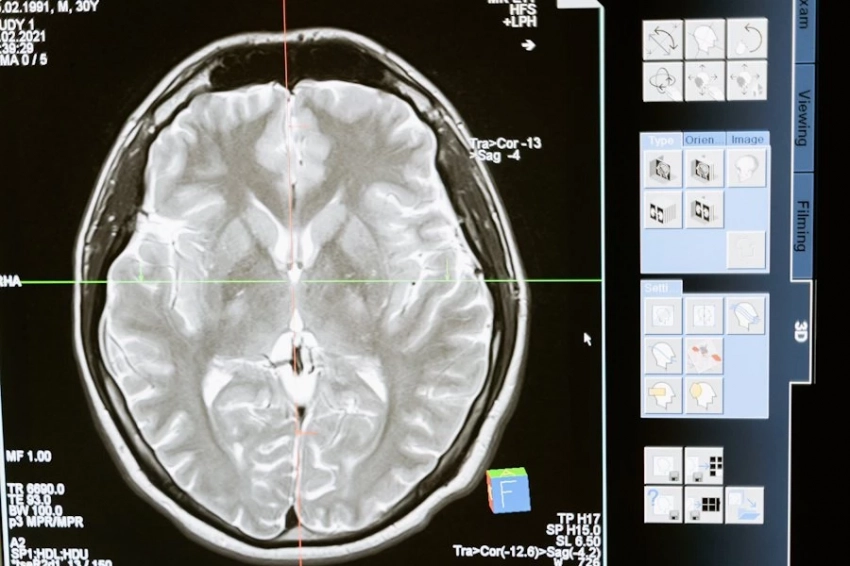

Сегодня инсульт занимает второе место в списке основных причин смертности в мире. Ежегодно он становится причиной инвалидности, деменции и других проблем со здоровьем у миллионов людей. Однако, несмотря на распространенность этого явления, уровень смертности от инсульта разнится в зависимости от страны: 86% смертей приходится на страны с низким и средним уровнем дохода. Важно отметить, что инсульты все чаще случаются у людей моложе 55 лет.